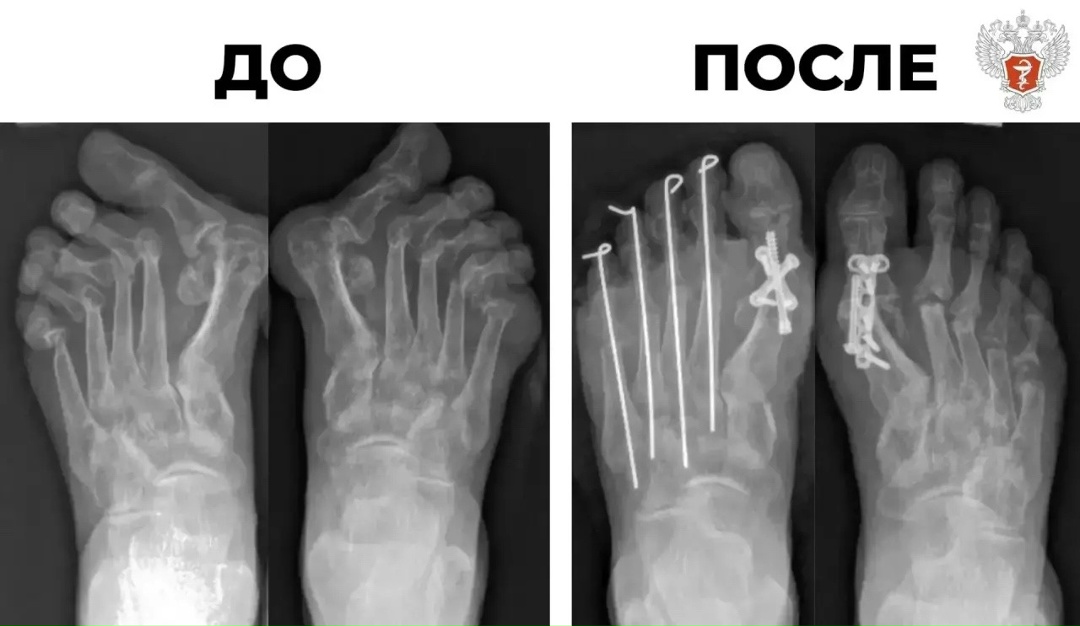

Пациентка поступила в Новосибирский НИИ травматологии и ортопедии им. Я. Л. Цивьяна Минздрава России с сильной деформацией десяти пальцев на ногах, вызванной ревматоидным артритом.

После лекарственной терапии врачи приняли решение о проведении операции Клейтона-Хоффмана для коррекции деформации, в ходе которой исправили вывихи малых пальцев и зафиксировали их спицами.

— Мы убрали разрушенные давящие головки плюсневых костей, тем самым добились снижения напряжения на тканях. Пальцы встают в правильное анатомичное положение, уходит подошвенное давление, — рассказал хирург-ортопед Новосибирского НИИ травматологии и ортопедии им. Я.Л. Цивьяна Минздрава России Матвей Лучшев.

❤️ Операция прошла успешно. Сейчас стопы пациентки работают правильно. В скором времени она сможет носить обычную обувь и продолжать лечение.